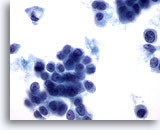

Figure 49

Breast FNA, Lobular carcinoma.

Cells with a plasmacytoid appearance and round nuclei are shown here. The background material appears to be proteinaceous in nature, rather than necrotic. A small single file of 3 cells is seen in the center of the field. 60x

Figure 49

Breast FNA, Lobular carcinoma.

Cells with a plasmacytoid appearance and round nuclei are shown here. The background material appears to be proteinaceous in nature, rather than necrotic. A small single file of 3 cells is seen in the center of the field.

60x